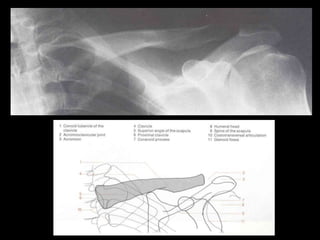

This document provides an overview of normal musculoskeletal imaging. It discusses basic x-ray concepts and densities. It then reviews normal anatomy as seen on x-rays of the skull, spine, pelvis, chest, and extremities. Key anatomical structures are labeled on example x-rays for the shoulder, hip, knee, and foot. Quizzes are included to test recognition of anatomical structures and patient age based on x-rays.